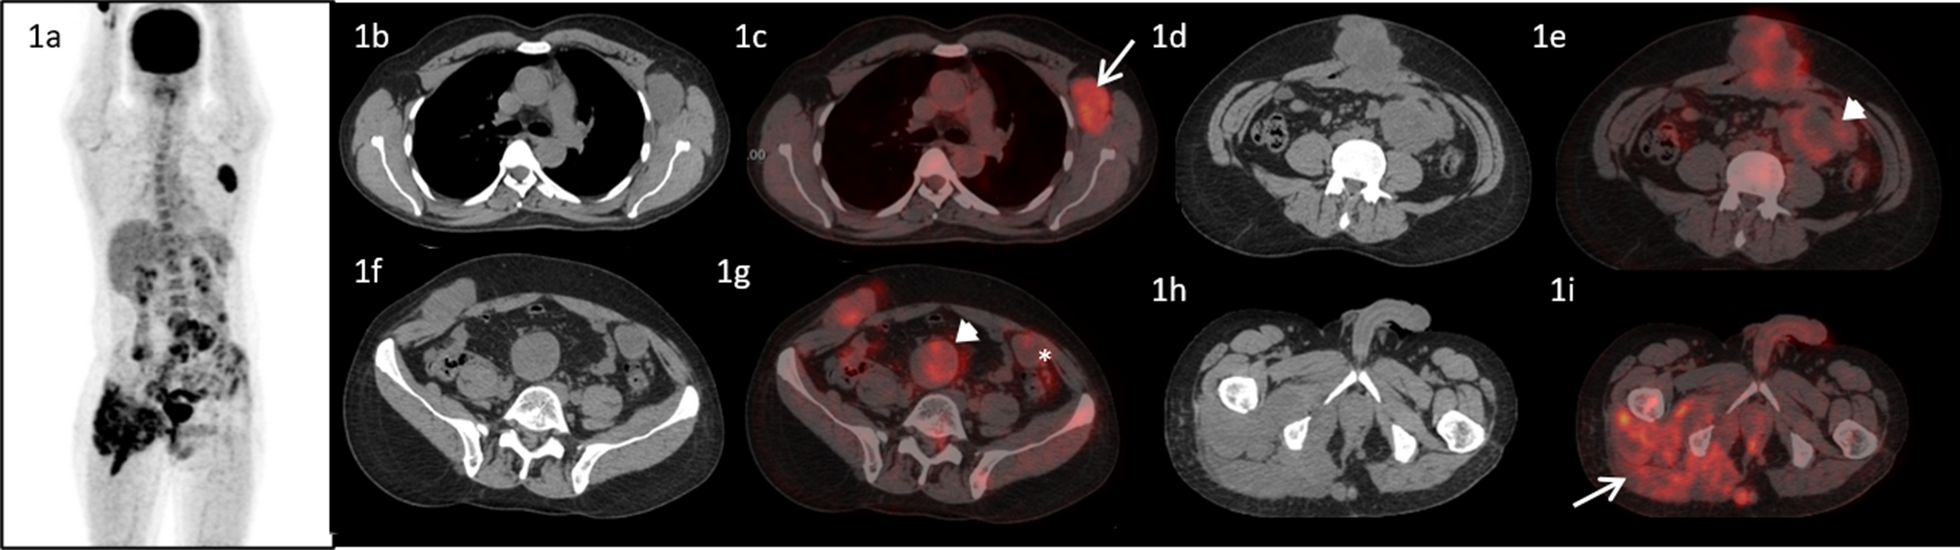

A pre-imatinib 18F-Flurodeoxy glucose (FDG) positron emission tomography/computed tomography (PET/CT) maximum intensity projection (MIP) image of the patient showing increased FDG uptake in the left axillary, lower abdominal and pelvic regions. Transaxial computed tomographic images at the level of axilla, L3 vertebra, L5 vertebra and ischial tuberosity (1b, 1d, 1f and 1h) and corresponding fused PET/CT images (1c, 1e, 1g and 1i) showing enlarged and FDG avid left axillary lymph node (1c, arrow), FDG avid lobulated mass in the anterior abdominal wall (1d and 1e), deposit in the right external oblique muscle (1f and Ig), multiple mesenteric (arrow heads) and omental* deposits (1e and 1g). There was soft tissue thickening adjacent to the right ischium involving the right pyriformis and gluteal muscles with increased FDG uptake and soft tissue deposit the subcutaneous plane adjacent to it (1h, 1i -arrow)